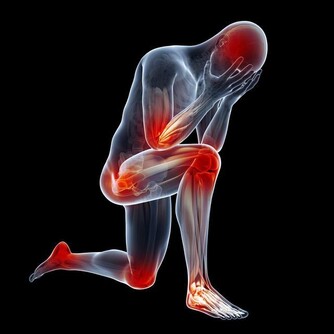

腳是人體"第二心臟",有多個穴位。每天溫熱水泡腳、按摩可促進血液循環,還可起到強身健體、保健養生的功效。當雙腳出現一些不適症狀時,可能在暗示您身體有隱疾,要引起足夠的重視。3個腳部症狀暗示你身體有隱疾!

所以說,腳對於一個人的健康是非常有影響的。下面一起來看看腳部的哪3個信號,暗示你的身體有哪些隱疾,一般人都不知道!

第一信號:腳麻

1.中風前的徵兆

濟南同濟吳峰醫生介紹說:對於患有高血壓、高血脂、動脈硬化等疾病的人來講,腳麻可能是中風的先兆。這類患者多表現為一側或兩側肢體無力且麻木,多半不會只發生在腳上,如果細心詢問,患者還多會伴有一過性的黑蒙、失語、聽力改變、說話模糊等。

在醫學上叫“小中風”,常發生在爆發性中風之前,患有高血壓等心腦血管病的人一定要注意。

2.腰椎間盤突出

濟南同濟吳峰醫生介紹說:患腰椎間盤突出時,坐骨神經受到壓迫。而坐骨神經是支配下肢的主要神經乾,它的通路是沿著腰、臀部、大腿後、小腿後外側一直到足外側。

因此,腰椎間盤突出患者容易出現腳麻,大多還會伴有腰疼、腿疼等。還有一些患者表現為時而左腳發麻,時而右腳發麻,這類人多屬中央型腰椎間盤突出。

3.糖尿病並發症

濟南同濟吳峰醫生介紹說:對於糖尿病患者來講,當血糖升高時會引起神經纖維一系列的代謝紊亂,從而導致周圍神經病變。這時就會四肢末端麻木等。

一般來講,下肢會比上肢嚴重,如果患者已經知道自己患有糖尿病,應積極治療原發病。如果有糖尿病家族史、或肥胖,也應考慮糖尿病的可能。

第二信號:腳腫

濟南同濟吳峰醫生介紹說:腳腫只是一種症狀,可能屬於生理性的腳腫,多是因疾病引起的。

第一是心源性疾病引起的腳腫,比如慢性心臟功能不全、心衰等,這些都會引起腳步的浮腫。因此,無端的出現了腳步浮腫千萬不要大意,最好去醫院好好查一下心臟。

第二是腎臟疾病引起的腳腫,如腎功能不全、腎病綜合症等,這一類人也是最常見的。同時判斷是不是腎臟引起的腳步浮腫,還可以看看眼睛,一般腎臟有問題,眼睛同樣也睡浮腫。

第三是血管疾病可引起腳腫,比如靜脈瓣功能不全、靜脈回流障礙、深靜脈血栓。

第四是肝臟疾病,肝臟是人體蛋白合成的重要器官,如果患有慢性肝臟疾病,血液中的白蛋白數量下降,血液滲透壓下降,也會引起腳腫。

第三信號:腳疼

糖病足早期信號

濟南同濟吳峰醫生介紹說:當一些糖尿病患者出現行走一定距離後就腿痛、腳痛,就要留意了。許多人會把這些症狀當成是“老寒腿”,或者以為是腰椎疾病所致,其實出現這些症狀對於常人來說可能是一般的疾病,而對於糖尿病人來說,卻可能是糖尿病足的信號。

下肢動脈硬化

在我們身邊,經常會發現老年人走了一段路,就感覺自己腳有點兒疼,但不論是老年人自己還是周圍的親屬,首先想到的就是“會不會是腰間盤突出啊”?但實際上,在進入古稀之年後,越來越多的老人會患上下肢動脈硬化閉塞症或急性動脈栓塞。

濟南同濟吳峰醫生介紹說:下肢動脈硬化閉塞症,就是腿上的動脈血管由於動脈血管堵住了,導致腿腳供血不足,從而出現一系列症狀。一般就是不走路的時候還好,不覺得疼;一旦走路較多,就會出現腳疼、小腿酸痛。